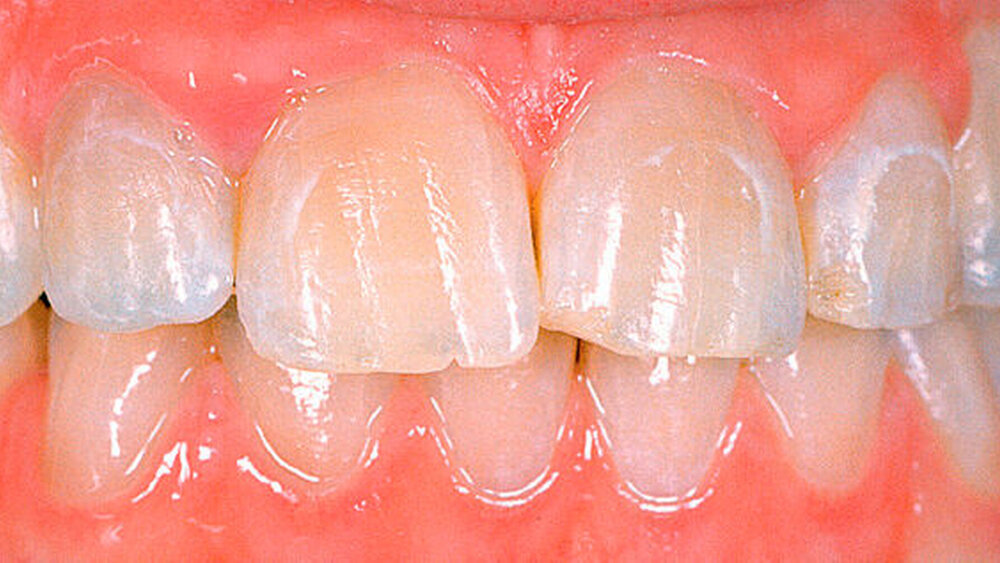

Die Amelogenesis imperfecta kann neben der hypoplastischen Form in eine hypomaturierte Form und eine hypokalzifizierte Form eingeteilt werden. Auch Kombinationen der verschiedenen Formen der Amelogenesis imperfecta wurden beschrieben. Bei der hypomaturierten Form ist die Schmelzhärte weicher als normal, die Schmelzdicke entspricht beim Durchbruch der Zähne der Norm. Bei der hypokalzifizierten Form ist der Schmelz sehr weich und die Schmelzdicke beim Zahndurchbruch normal. Deshalb sind vor allem bei der hypomaturierten und hypokalzifizierten Form die Abrasion und Attrition stark erhöht. Bei beiden Formen ist die Zahnfarbe beim Durchbruch der Zähne opakweiß bis gelblich. Mit zunehmendem Alter werden die Zähne braun. Die Prävalenz der Amelogenesis imperfecta beträgt je nach Population und Typ zwischen 1: 700 bis 1 : 20.000.